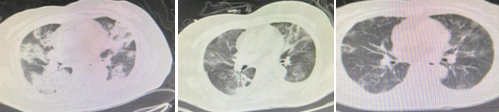

术后,神经外科团队在围术期进行精准的专科及系统的全身管理,促进神经系统进一步恢复,同时防治全身并发症的发生。然而一波未平,一波又起。患者高龄,平素又患有高血压、糖尿病及银屑病,长期服用药物,机体免疫力低下,容易并发其他系统疾病。术后患者出现高热、意识变差、自觉呼吸困难、呼吸急促、喘憋等症状,指氧饱和度低至87%左右。医生们的心又紧绷起来,随即,核酸结果证实新冠病毒阳性,胸部 CT检查提示双肺呈弥漫性渗出改变,即常说的“大白肺”。面对新发状况,神经外科立即组织科内讨论,制定周密的治疗方案,给予高流量吸氧改善缺氧症状,应用抗生素控制炎症,并针对新冠病毒感染,给予积极、全面的治疗。同时联系呼吸与危重症医学科联合会诊,并安抚患者及家属焦虑的心情,增强战胜病魔的信心。经过积极、有效地处理,患者病情趋于平稳,体温下降,指氧饱和度逐渐恢复至正常,憋气、气促等呼吸困难症状缓解,患者的活动也逐渐增加。随后的动态胸部CT检查提示,炎性渗出逐渐减少,病变范围不断缩小,患者再一次化险为夷。2023年1月13日,临近春节,患者痊愈,步行出院。

治疗前胸部CT ;治疗中胸部CT ;治疗后胸部CT(图从左至右)